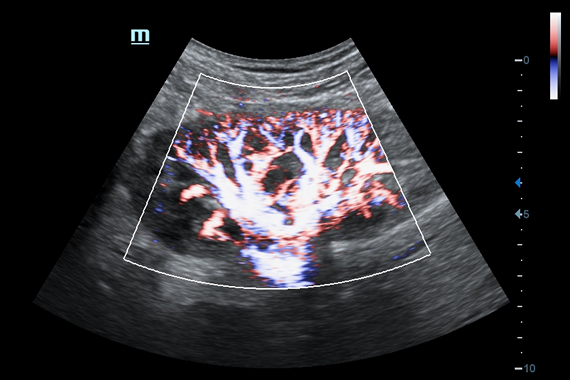

• HR Flow - режим отображения кровотока с высоким временным и пространственным разрешением для точной и однородной визуализации сосудов, в том числе самых мелких.

• HR Flow - режим отображения кровотока с высоким временным и пространственным разрешением для точной и однородной визуализации сосудов, в том числе самых мелких